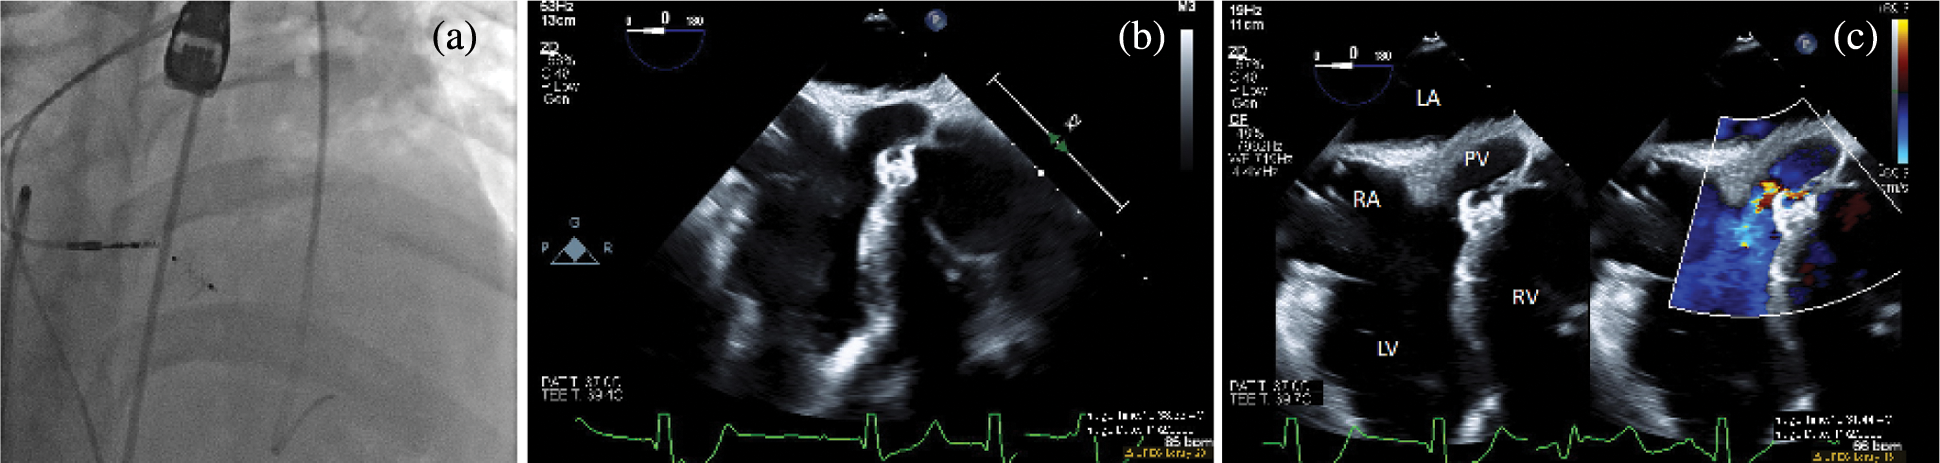

For a number of reasons, this approach was challenging in this patient. The VSD was remote from the aortic valve and could not be engaged using a Judkins coronary catheter. Instead, an Amplatz left 1 (AL-1) catheter (Cook Medical, Bloomington, IN, USA) was used to engage the defect under fluoroscopic guidance and confirmed on TEE. The floppy J-tip of the wire would not pass cleanly. The wire buckled and forced the catheter out of position even when the VSD was cleanly engaged on fluoroscopy and TEE. Instead, a 0.035 inch angle-tipped hydrophilic glide wire (Terumo Corp, Elkton, MD, USA) was selected and directed across the defect without incident (Fig. 2a). The AL-1 catheter tracked over this wire into the subpulmonary LV. Rather than forming a veno-arterial loop, we decided to utilize a retrograde deployment of an ADOII device. To do this, we exchanged the catheter and wire for a 0.035 inch Rosen guidewire (Cook Medical, Bloomington, IN, USA), and with some manipulation of the coronary catheter, we were able to achieve a redundant loop of wire in the LV cavity (Fig. 2b). A TorqVue delivery system tracked retrograde over the wire and through the defect without issue (Fig. 2c). Under a combination of fluoroscopic and TEE guidance, the device was unsheathed and then deployed. Initially, the device would not pull back cleanly to appose the septum, which we determined was due to it being trapped in the mitral valve apparatus. The device was re-sheathed without difficulty, and the left ventricular disc was opened closer to the septum. The partially unsheathed device and delivery system were pulled back as a unit without difficulty until flush against the septal wall. The rest of the device was unsheathed and appeared to be in a good position vis the septum (Fig. 2d). There was no hemodynamic derangement, and the patient remained in his usual paced rhythm without issue. After TEE and fluoroscopic inspection, the device was released. It reoriented once released from its delivery cable but remained in a good position (Fig. 3).

Figure 3: Post-intervention imaging. A fluoroscopic image in an RAO/Cranial projection after device release (a). The device reorients and remains in a good position with no residual shunt on angiography. Transesophageal echocardiogram in a zero-degree view after device release in 2D (b) and with color compare (c). The device appears well seated across the ventricular septal defect, and color Doppler shows trivial residual flow around the superior edge of the device. LA, left atrium; LV, left ventricle; PV, pulmonary valve; RA, right atrium; RV, right ventricle

Angiography demonstrated the device in a good position with no residual shunt. TEE evaluation demonstrated no new aortic insufficiency and no change in the baseline mild tricuspid insufficiency. A trivial residual shunt was seen on TEE. During recovery and overnight observation, the patient demonstrated no change in baseline rhythm. He returned for uncomplicated percutaneous lead extraction of the malfunctioning ventricular lead and upgraded to a biventricular implantable cardioverter-defibrillator two months after his catheterization procedure. There was no residual shunt on intracardiac echocardiography (not pictured), and he returned home the next day.